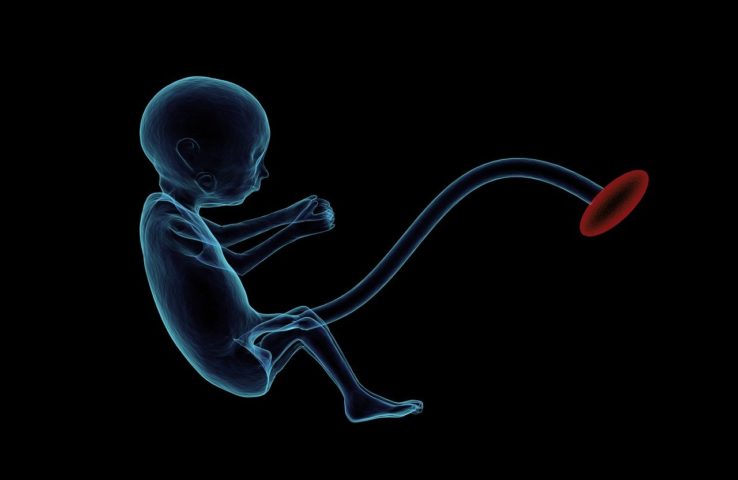

Mulher passa cinco décadas com feto calcificado na barriga